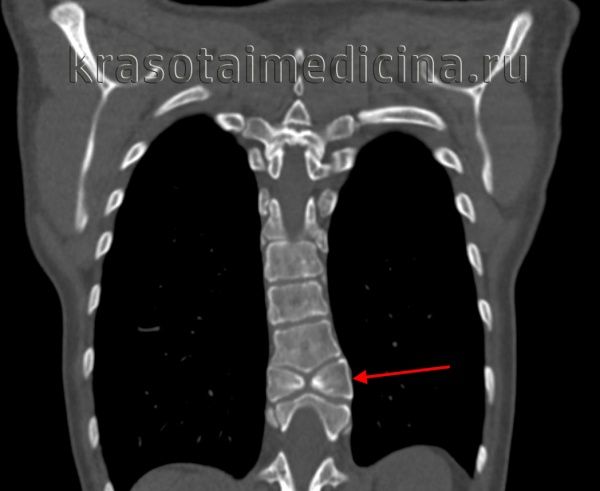

3. КТ признаки аномалии Клиппеля-Фейля:

• Костная КТ:

о Типичные костные признаки ± дегенеративные изменения

о Сагиттальный и поперечный размеры спинномозгового канала обычно остаются нормальными

- Сужение спинномозгового канала свидетельствует о дегенеративных изменениях смежных с блокированными сегментов

- Расширение канала → скорее всего связано с сирингомиелией